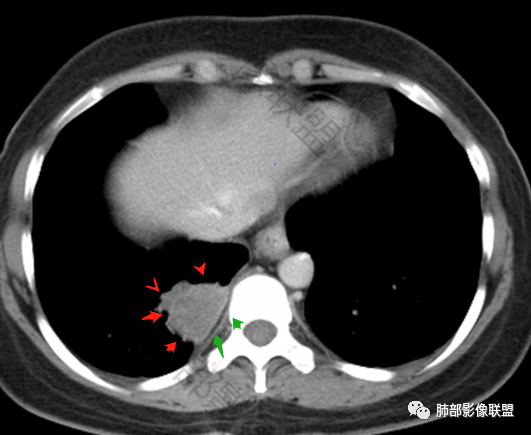

2.右肺下叶脊柱旁类椭圆形块影,边界清楚,密度偏低,隐约见轻度强化囊壁样结构,均匀一致,中央区域未见强化,因属囊样块影。前外缘处显示“壁外”小范围轻度强化软组织密度影,未见磨玻璃晕。

3.块影边缘见匍行血管影,未显示体循环供血。病灶与支气管关系未能显示或呈现。

病灶相邻胸膜轻度强化,未见壁层胸膜侵入或突破。

定位肺内,脂肪间隙没有问题,胸水在病灶后方,病变起源脏层胸膜以内,所以定位肺内

胸膜均匀强化,在病变后方